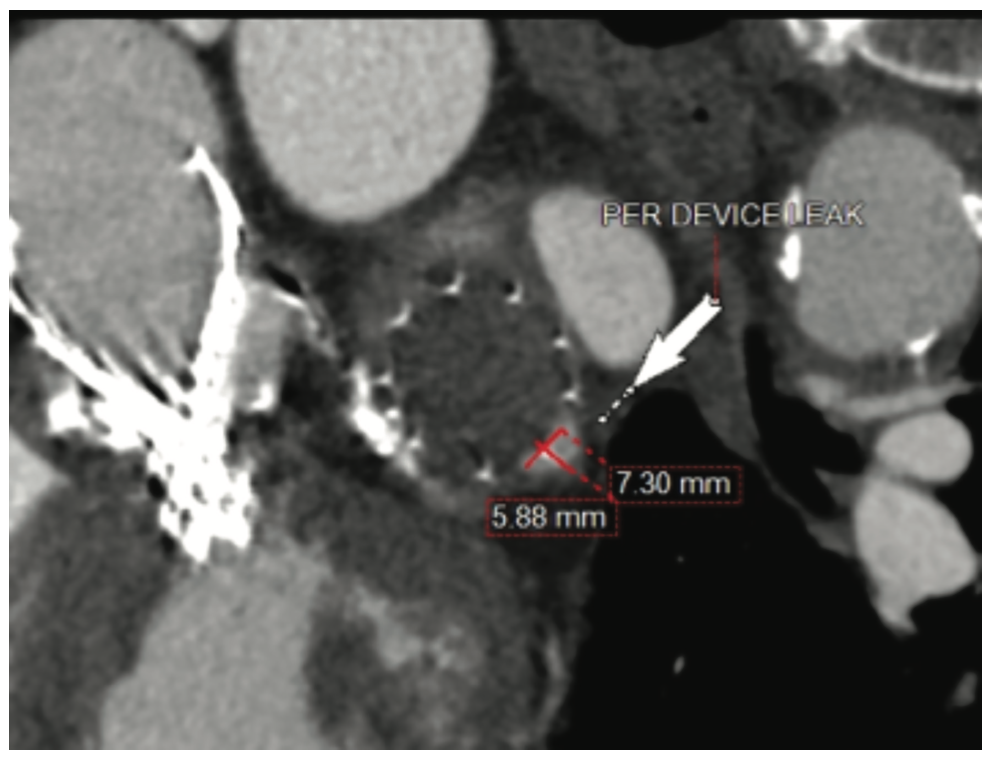

One of the challenges in placement of the Watchman device is due to the variation of shapes and sizes of the LAA; the use of a fixed device can lead to valvular leak. When there is failure to occlude the LAA, it can be due to a paradevice leak (Figure 2), often described as the “presence of a contrast-enhanced trail adjacent to the device”.5 Leaks are categorized as minimal (<1 mm), mild (1-3 mm), moderate (4-5 mm), or severe (>5 mm). If the paradevice leak is >5 mm, it is considered an “incomplete closure” of the LAA. This is viewed as significant, and computed tomography (CT) should be utilized to evaluate the leak. The CT is thought to hold a higher level of sensitivity than echocardiography. Common causes of paradevice leaks include failed endothelialization, malpositioning in the ostium (off axis), incorrect device sizing, size and shape of the LAA, or an inability to cover multiple lobes with a single device.

The patient’s speech improved; however, there was concern as to the cause of the diffuse acute stroke. A CTA of the thorax was ordered to evaluate the LAA/Watchman device. A leak was present in the LAA measuring approximately 5.88 mm (Figure 3), similar in size to the leak noted prior to the AVP2 device placement. Subsequent CTs of the lower abdomen, pelvis, and extremities revealed the AVP2 was lodged at the origin of the left common iliac artery (Figure 4). The plug had become dislodged from the LAA and traveled through the aortic arch to the abdominal aorta. Retrieval of the plug was planned for 5/31/22.